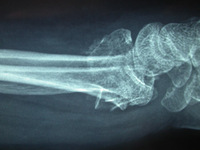

Wrist fractures

Type C (complex) intra-articular fracture of the distal radius: lateral view

From the collection of Dr Chaitanya S. Mudgal